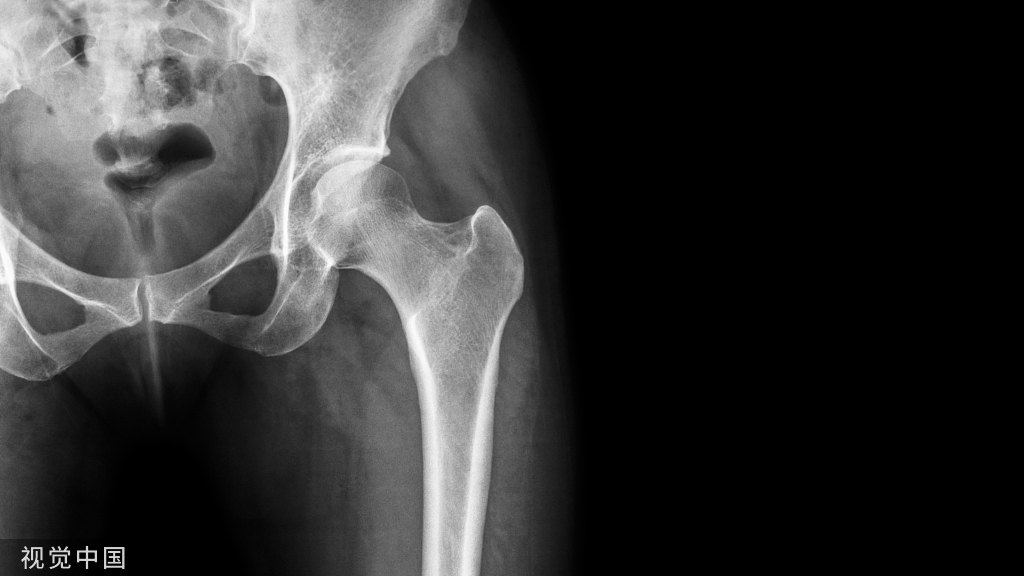

骨科活检技术是骨科医师应该掌握的一项重要技术,主要用于骨肿瘤、软组织肿瘤以及其他骨与软组织病变的诊断和鉴别。

根据患者提供的临床信息和影像学表现,怀疑患者有侵袭性、恶性肿瘤可能或者不能明确诊断时应该考虑使用骨活检技术,获取病变组织的标本行病理检查,以便在术前获得准确的诊断,继而制订周密的治疗计划。

但是需要注意的是,非肿瘤的骨病变也能导致常规影像学上的局部异常,包括创伤、代谢性骨病、骨循环疾病、滑膜病等,尤其是骨感染特别需要鉴别,骨科医师在见到骨的局部病灶时应时刻考虑到这些疾病。

如果怀疑是骨肿瘤,应将其归入以下三种主要类别:①良性骨肿瘤;②恶性原发骨肿瘤;③骨转移瘤。

活检的适应证:临床表现和影像学表现都为良性的骨与肌肉病变,如骨囊肿、脂肪瘤,不需要行活检;只有表现为良性侵袭性、恶性和诊断不明确的时候才行活检,以明确诊断和对疾病进行分类。

活检位置的选择有重要的意义,因为不恰当的骨与软组织肉瘤活检可能会将肿瘤种植于活检组织周边,造成不必要的复发。正确的活检位置应位于恶性肿瘤手术的切除范围内(图2-7-1)。